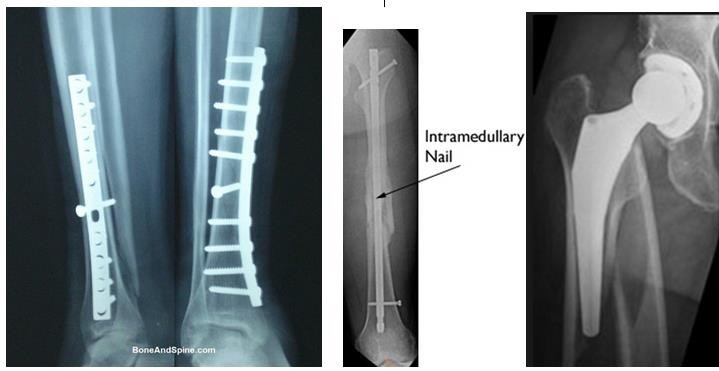

- Phẫu thuật:

- Nẹp vít (AO)

- Đinh nội tủy

- Buộc chỉ thép, xuyên đinh

- Ghép xương

Ưu điểm của phẫu thuật là cho phép nắn xương đúng vị trí, bất động tương đối chắc chắn, tránh được di lệch thứ phát, người bệnh có thể tập cử động và chịu trọng lượng sớm, tránh các biến chứng teo cơ, cứng khớp, loãng xương.